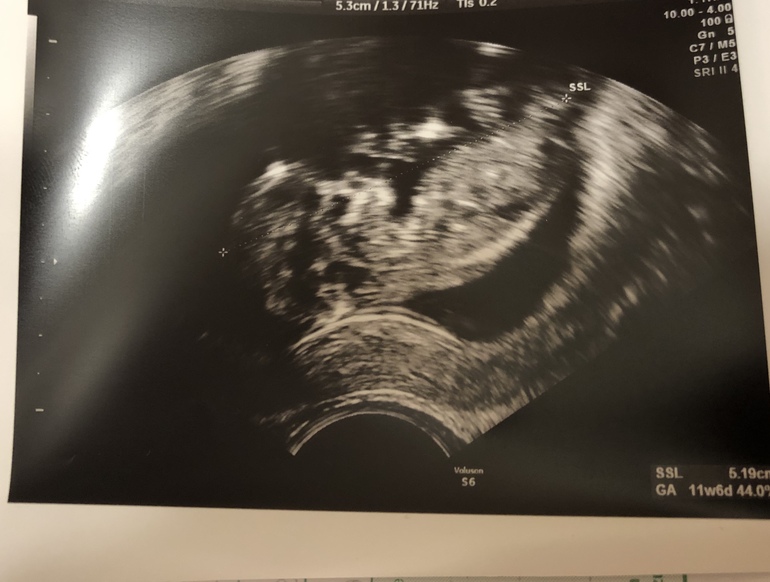

Пол по узи 11 недель

Пол малышаДай, думаю, спрошу знатоков)

Половой бугорок не видно вроде, но может кто по форме головы разбирается?)

Мне самой кажется, что мальчик 👦🏻

Нет, это есть такой «метод», Skull Theory. Типа метода Рамзи. Мне чисто для статистики, потом с результатом сравнить 🤣

Я на немецком форуме выставляла фото по форме головы, эта теория работает с 20 недели, но...... бред полный, все единогласно сказали мне мальчик, а у меня доча. А так чисто интуитивно мне кажется у вас мальчишечка

Я читала, что с 12 недели работает.

Ну, посмотрим через 2 месяца, кто там прячется у меня) пока здесь все за мальчика 👦🏻